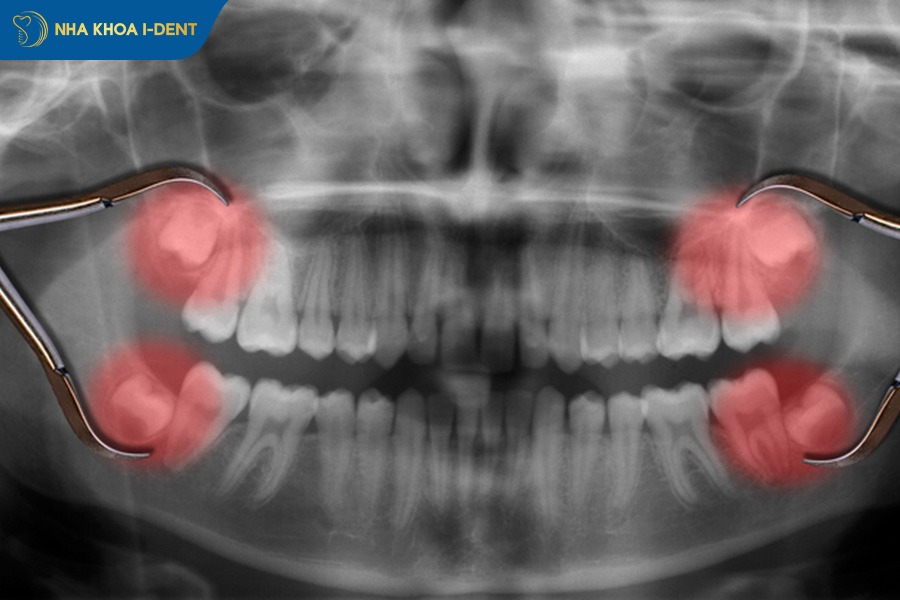

2.5. Răng mọc ngầm

Răng mọc ngầm là tình trạng răng không mọc đúng vị trí trên cung hàm mà nằm ẩn hoàn toàn hoặc một phần trong nướu, xương hàm và một ngày nào đó sẽ tách nướu trồi lên. Tình trạng này thường gặp ở răng nanh và răng khôn.

Khi răng mọc ngầm thì các răng bên cạnh có thể bị xô lệch, chen chúc làm mất cân đối cung hàm và gây khó khăn trong việc vệ sinh. Răng mọc ngầm cũng có thể tạo nang quanh răng gây đau âm ỉ, viêm nhiễm hoặc đẩy các răng còn lại ra khỏi vị trí ban đầu.

Trong chỉnh nha, việc xử lý răng mọc ngầm được thực hiện bằng cách mở đường bộc lộ răng ngầm và gắn khí cụ để kéo răng lên đúng vị trí trên cung hàm. Đây là kỹ thuật đòi hỏi bác sĩ có chuyên môn cao và được thực hiện theo từng giai đoạn để đảm bảo răng dịch chuyển an toàn. Trong một số trường hợp, bác sĩ sẽ khuyên bệnh nhân nhổ bỏ thay vì niềng.